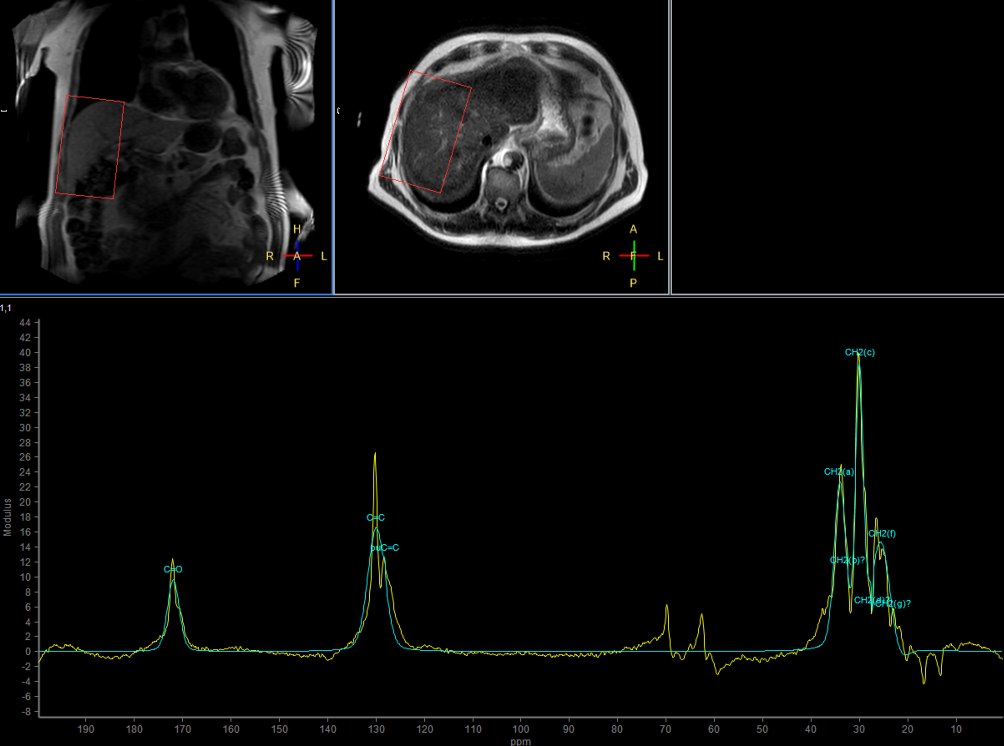

Multi Nuclei - Liver imaging (13C)

Make multi-nuclei imaging and spectroscopy become part of your clinical operations via a seamless integrated workflow for multi-nuclei image acquisition, spectroscopy, reconstruction, and viewing. The nucleus is just a scan parameter like any other sequence parameter. A single ExamCard can be used to run both proton and non-proton imaging. Reconstruction and viewing of non-proton images or spectra, as well as the process for sending the data to PACS is fully integrated, so workflow does not differ from proton imaging. The transmit-receive 13C flex coil, with a 14 cm diameter, is immediately recognized by the ExamCard interface. Improved SNR and simplified spectra* are achieved by combining body coil decoupling with the transmit-receive surface coils.